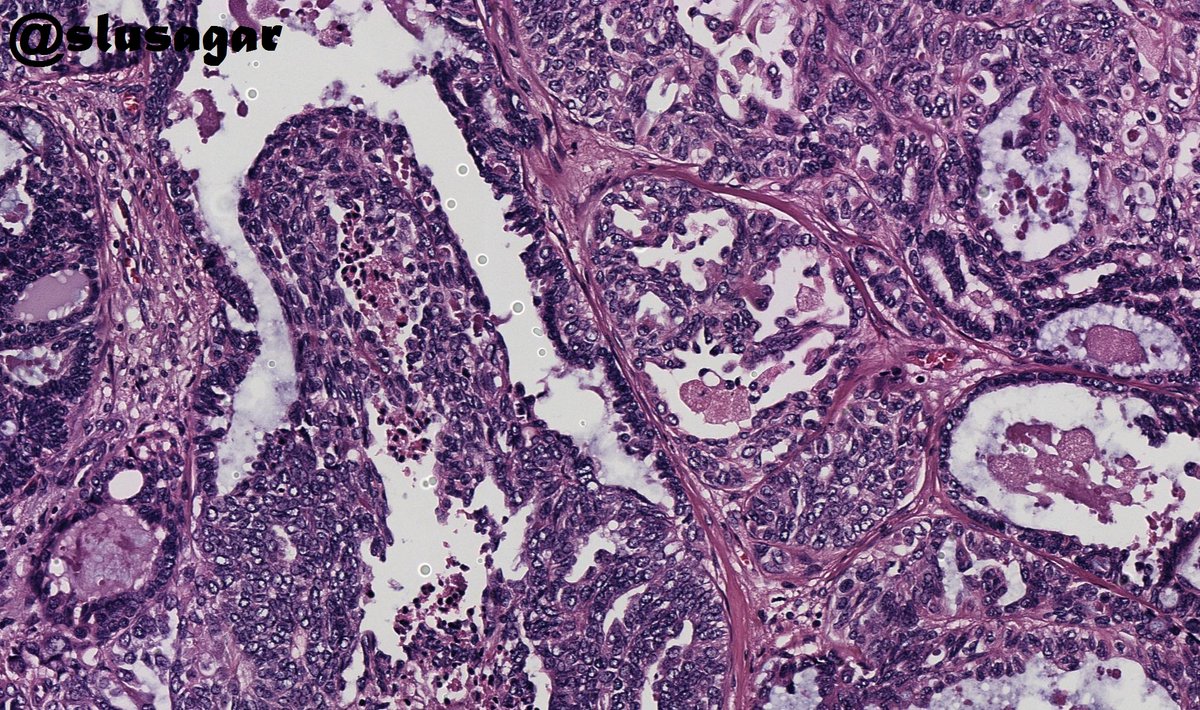

1/ Your favorite #breastpath topic....papillary lesions...core needle biopsy from a BI-RADS 5 lesion... What is your diagnosis #pathtwitter?

1/ Your favorite #breastpath topic....papillary lesions...core needle biopsy from a BI-RADS 5 lesion...

What is your diagnosis #pathtwitter?